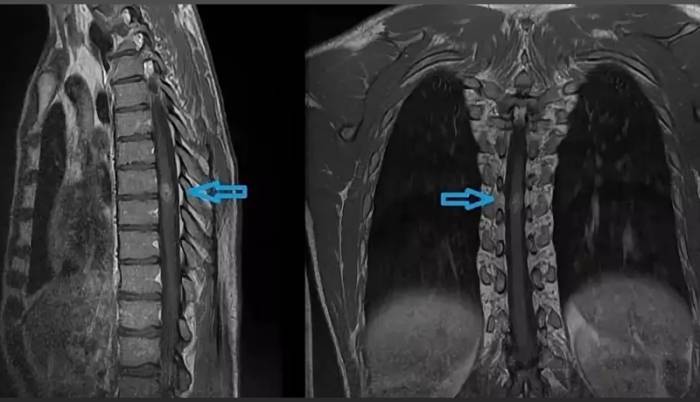

Опухоль спинного мозга на МР-томограмме (обозначена стрелкой)